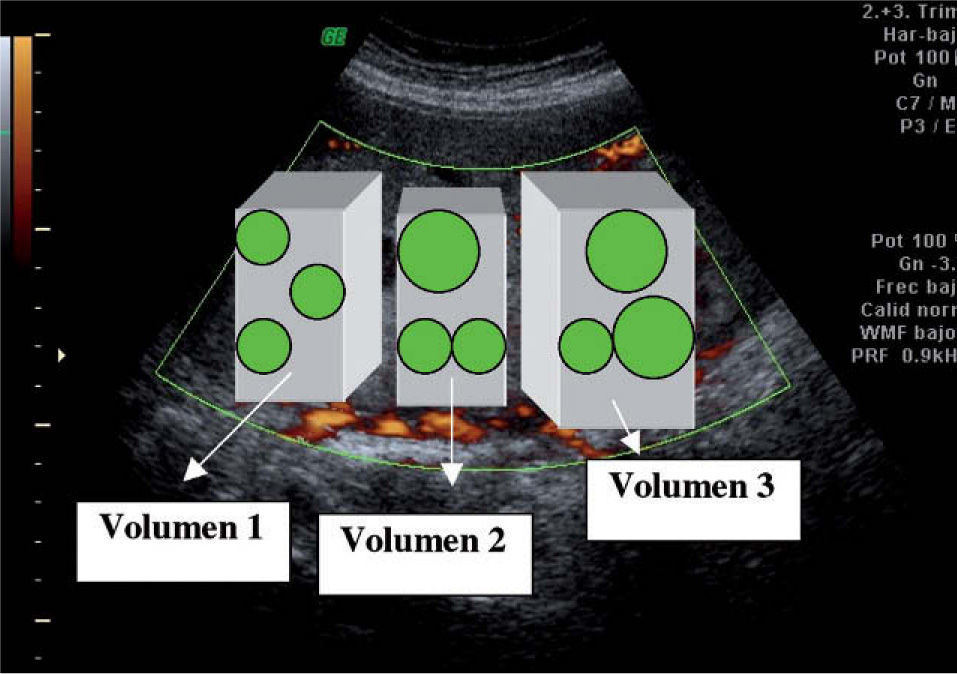

En un tiempo posterior, se realizó el análisis de los volúmenes almacenados, utilizando el programa informático VOCAL incorporado en el equipo. Cada volumen recuperado se representa en la pantalla en la forma multiplanar. Trabajando sobre el plano A, se colocaron los límites de un eje de rotación entre la placa corial y la basal. De esta manera, y rotando sobre ese eje, se generó una esfera de tejido de distinto volumen, que se consideró válida para el estudio si comprende todo el espesor y no incluyó las grandes arterias visibles tanto en la placa basal como en la corial (fig. 2). Por cada volumen de placenta adquirido y almacenado, se obtuvieron y analizaron posteriormente 3 esferas adyacentes de tejido; por tanto, por cada paciente fueron 9 esferas a modo de otras tantas 9 «biopsias placentarias», tal y como podemos observar en forma esquemática en la figura 3.

Respecto al estudio de vascularización y analizando el sistema VOCAL, se obtuvieron y almacenaron en el equipo ecográfico para su posterior evaluación off-line, 3 volúmenes placentarios, y de cada uno de ellos se extrajeron, a su vez, otras tres distintas esferas de tejido a modo de «biopsia placentaria». Son, por tanto, 9 esferas, cada una de ellas de distinta capacidad, dependiendo del grosor de la placenta correspondiente de la cual se extrae. De una manera automática, y una vez seleccionada la esfera a estudiar, el equipo calculó los diferentes índices de vascularización reportados.

Con la intención de ofrecer una metodología más sencilla y comprobar si los resultados no varían si se evalúan un menor número de esferas, se estudió la reproducibilidad de esta técnica y se calculó para ello el acuerdo intraobservador para 3 formas diferentes de obtención de los parámetros de vascularización:

- 1.

Analizando tan sólo una esfera del primer volumen.

- 2.

Analizando las 3 esferas del mismo volumen (se toma el volumen 2, el más central).

- 3.

Analizando una esfera de cada volumen.